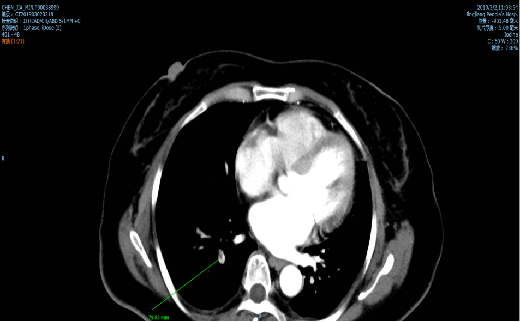

[印象]1.腹膜后、两侧髂血管旁多发肿大淋巴结,腹主动脉左旁淋巴结较前(2018-12-24)略缩小。肠系膜血管旁淋巴结较前相仿。 2.肝左叶萎缩伴动脉期异常灌注;脂肪肝;肝尾叶细小脂肪密度,较前相仿。副脾,双肾囊肿。 3.右肺下叶后基底段肺动脉栓塞(不完全性),右肺下叶背段肺囊肿,两侧胸腔微量积液及局部胸膜增厚,纵隔内散在正常大小淋巴结。 4.甲状腺饱满,左叶内强化小结节,请结合B超检查。双侧后下颈部、颈动脉鞘正常大小淋巴结。扫及右侧上颌窦粘膜下囊肿。 5.颅脑增强未见明显占位灶,请结合MRI检查。

查出肺栓塞